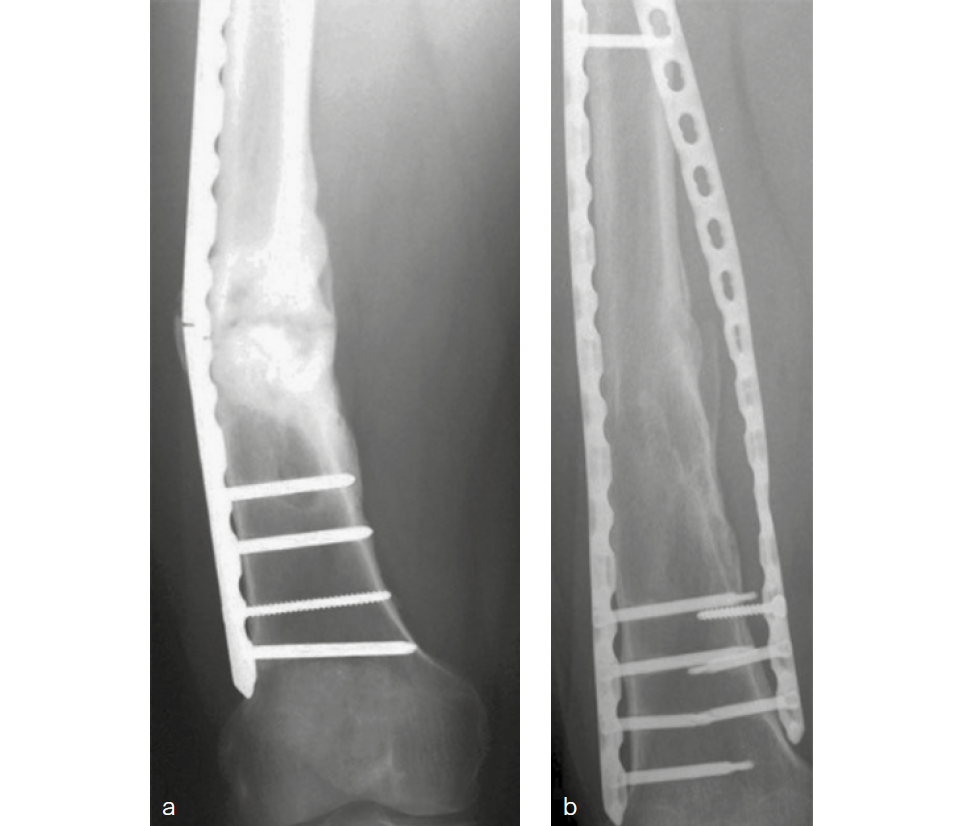

Single-plate fixation bridging bone defects provokes nonunion and risks plate-fatigue failure due to under dimensioned implants. Adding a helical plate to bridge the fracture increases stiffness and balances load sharing (Fig 1). The aim of this project was to compare stiffness and plate surface strain of different constructs in a transverse contact and gap femoral shaft fracture model.

Constructs with both lateral and helical plates demonstrated similar axial and torsional stiffness, independent of the contact or gap situations, being significantly higher compared with lateral plating (P <.01). Torsional stiffness of the constructs, with both lateral and helical plates in the gap situation, was significantly higher compared with this situation stabilized by a nail (P < .01). Plate surface strain dropp ed from 0.3% in the gap situation with a lateral plate to < 0.1% in this situation with both a lateral and a helical plate (Fig 2).